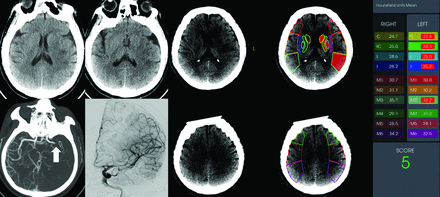

In the subgroup of patients with low ASPECTS of ≤5 (n = 68), 52 (76.5%) patients underwent MT, and 18 (34.6%) achieved a good neurologic outcome at 90 days. Lower mean ASPECTS-NWU values (8.44 [SD, 1.44]) were observed in patients with a good outcome compared with those with a poor outcome (10.15 [SD, 3.12]; P = .003). ASPECTS-NWU was consistently an independent negative predictor (OR, 0.56; 95% CI, 0.34–0.92; P = .022) of the 90-day neurologic outcome (Online Supplemental Data). The AUC of ASPECTS-NWU to predict a favorable outcome was 0.673 (95% CI, 0.542–0.805), with a sensitivity of 88.9% and a specificity of 48.0% at the optimal cutoff value of 9.86% in patients with low ASPECTS. A representative case is shown in Fig 4.

A patient with acute ischemic stroke due to occlusion of the M1 segment of the left MCA. This patient had an NIHSS score of 15 at admission and a low ASPECTS of 5. The mean value of ASPECTS-NWU at admission CT was 8.2%. Complete revascularization (mTICI grade 3) was achieved after mechanical thrombectomy. This patient had a favorable outcome, with an mRS score of 1 at 90 days. C indicates caudate nucleus; IC, internal capsule; L, lenticular nucleus; I, insula.